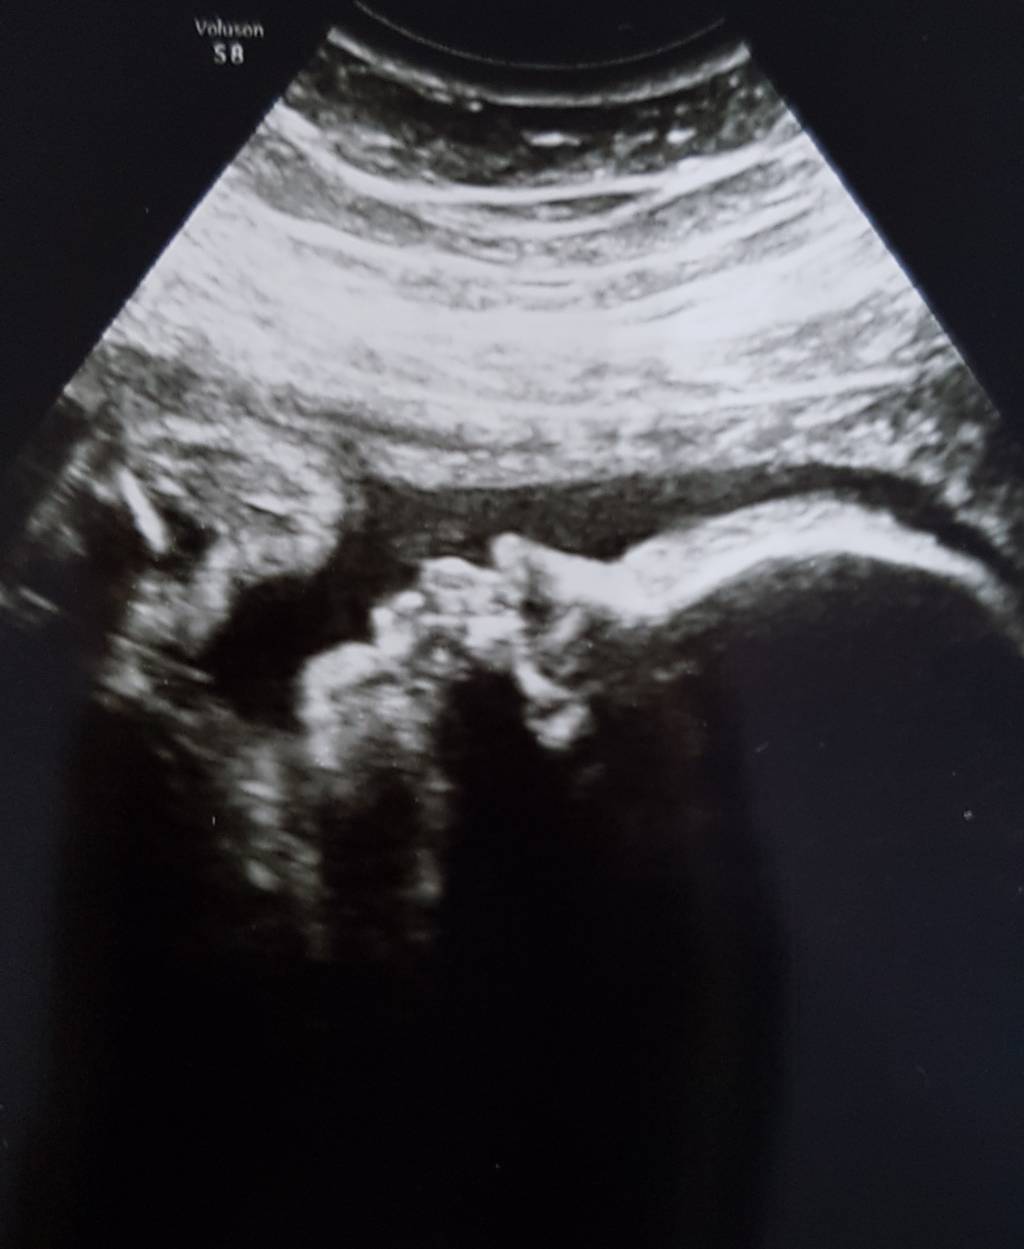

A to Kalinka i jej sweet dziubek.

1498130043-aaaaaa.jpeg